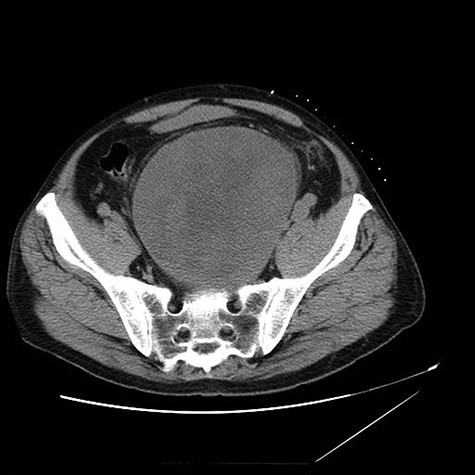

This case presentation involves a 57-year-old male who suffered multiple adverse sequela form the delayed diagnosis of a large presacral mass. He initially presented with left lower extremity deep venous thrombosis (DVT). Several months later, he developed a pulmonary embolus (PE). Due to his complaints of right groin pain, imaging was obtained that demonstrated a 13 × 14 cm presacral pelvic mass, which turned out to be a schwannoma on biopsy (Fig. 1). The presacral mass occluded the right-sided venous return from the leg and caused the DVT (Fig. 2) and PE. Due to the extensive DVT and PE, the patient had an inferior vena cava (IVC) filter that was placed and eventually clotted. He then was referred to our institution for surgical consultation.

Axial view of CT abdomen and pelvis shows a 13 × 14 cm presacral pelvic mass.